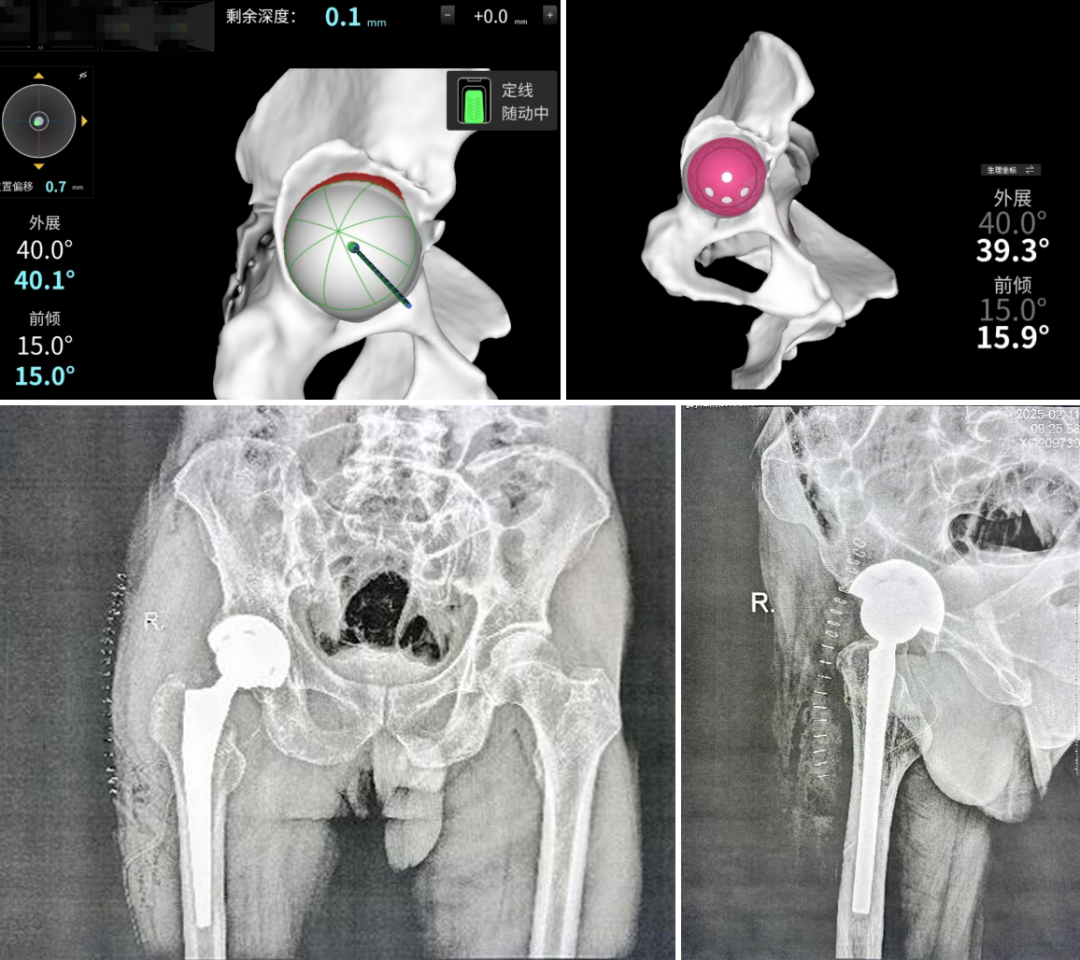

首台机器人辅助髋关节置换手术

患者谷先生,现年62岁,2个月前因意外摔伤导致右侧股骨颈骨折。经保守治疗后骨折未能有效愈合。谷先生慕名前往佳木斯骨科医院求治,经验丰富的王忠春教授检查后认为患者为陈旧性骨折,确认已失去自然愈合的可能性,需行全髋关节置换手术。经过仔细询问病史及详细的检查,发现患者有长达40余年的吸烟史,2年的脑梗死病史,并伴有低钾血症、支气管炎及低蛋白血症等多种内科合并症,这些因素增加了传统手术的风险。面对如此复杂的临床状况,骨科团队组织了多学科专家讨论,最终决定采用医院最新引进的国产智能关节机器人ARTHROBOT进行手术,以确保手术的精准性和安全性。

术前通过患者详细的CT扫描数据分析,根据患者的骨骼形态、解剖标志等个体特征,依托关节机器人智能手术规划系统,对假体型号、安装位置和角度、双下肢长度、联合偏心距等数据进行了亚毫米级别的精准测量和设计。术中,ARTHROBOT展现了其可视化、数字化、精准化的手术操作优势,10s内实现髋臼“一锉到底”,3分钟内完成髋臼杯和股骨假体的精准安放,术后评估臼杯位置误差在1度以内,双下肢等长,即刻髋关节屈伸活动自如,关节稳定,在高度屈曲和内旋情况下均无脱位风险。患者及其家属对手术效果非常满意。